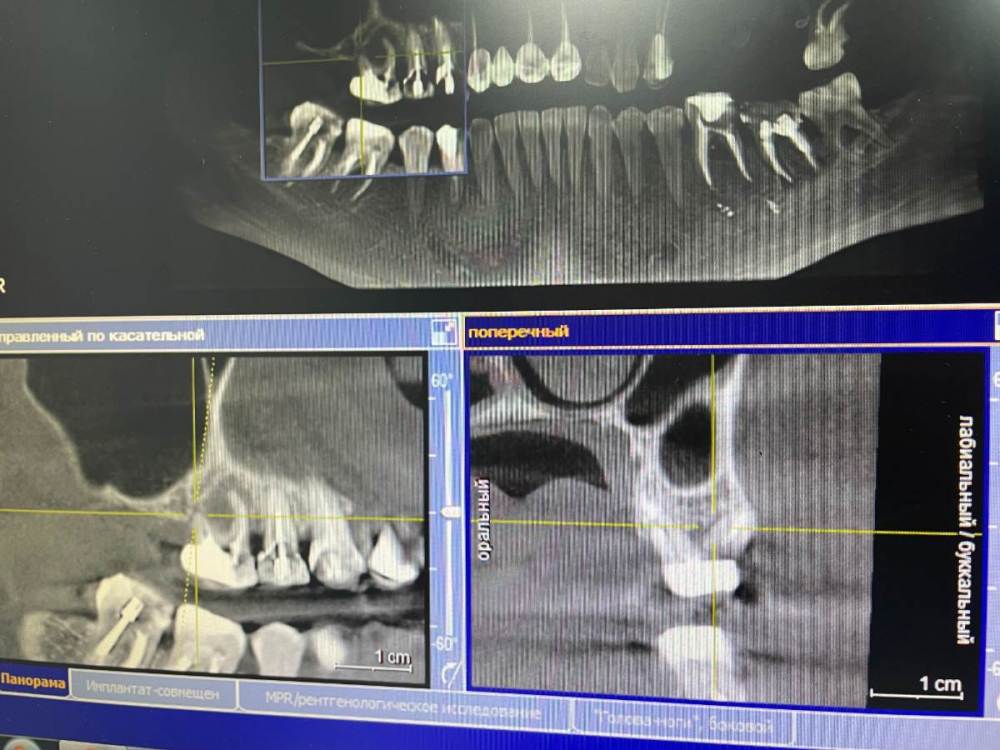

Irouil Опубликовано 21 октября, 2021 Поделиться Опубликовано 21 октября, 2021 Чтобы оценить прогноз перелеченных зубов надо увидеть ещё и снимки до лечения чтобы сравнить что было с тем, что стало. Такой вид снимка очень малоинформативен, я рекомендую либо выложить срезы из КТ интересующих Вас областей, либо выложить всю КТ 1 1 Ссылка на комментарий

Amparo743 Опубликовано 21 октября, 2021 Автор Поделиться Опубликовано 21 октября, 2021 @Irouil благодарю вас за ответ. К сожалению не знаю как извлечь из этой программы срезы или всю Кт. Мне отдали снимок на диске. И на этот снимок показывал врач и видел во всех этих зубах патологию, показывая именно с панорамы. Ссылка на комментарий

Irouil Опубликовано 21 октября, 2021 Поделиться Опубликовано 21 октября, 2021 Можете попробовать скинуть КТ в терапевтической ветке, тут надо его хорошенько посмотреть у каждого зуба чтобы оценить шансы на перелечивание, да и снимки до лечения было бы неплохо увидеть - может там динамика к улучшению стремится, но пока, судя по тем срезам что я вижу, вероятнее всего зубы действительно нужно будет удалять. Ссылка на комментарий

Bier Опубликовано 21 октября, 2021 Поделиться Опубликовано 21 октября, 2021 воспаление есть, скорее всего хирург прав, еще одно перелечивание они не перенесут. Ссылка на комментарий